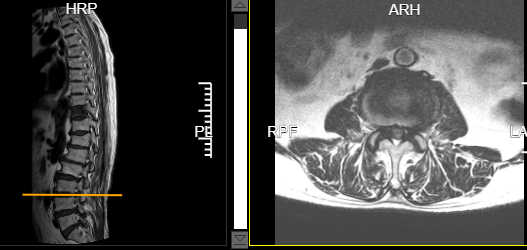

术后腰4/5椎管减压后狭窄解除